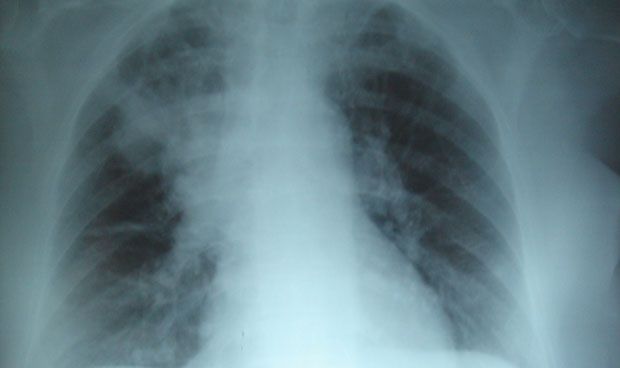

La fibrosis quística es una enfermedad genética que causa infecciones persistentes de pulmón y limita la capacidad de respirar con el tiempo y afecta a aproximadamente 70.000 personas en todo el mundo y 30.000 en Estados Unidos. La fibrosis quística es el resultado de mutaciones en el gen que codifica la proteína llamada regulador de conductancia transmembrana de fibrosis quística (CFTR, por sus siglas en inglés), que es importante para mantener la actividad del canal de cloruro que afecta al balance de sal y agua en los pulmones. Esta mutación tiene como resultado una proteína CFTR plegada erróneamente y su degradación prematura conduce a una permeabilidad perjudicial del cloruro y a una inflamación pulmonar persistente.

Múltiples defectos de tejido en los pulmones

Goldstein y los coautores Luigina Romani, en la Universidad de Perugia, y Enrico Garaci, en la Universidad de Roma 'San Raffaele', informan que Ta1, una versión sintética de un péptido natural aislado en primer lugar del timo, corrige los múltiples defectos de tejido encontrados en los pulmones e intestino delgado en un modelo de ratón de fibrosis quística, así como los defectos en el CFTR visto en las células aisladas de pacientes con fibrosis quística. Ta1 no sólo reduce significativamente la inflamación observada en la fibrosis quística, sino que también aumenta la maduración, la estabilidad y la actividad del CFTR.